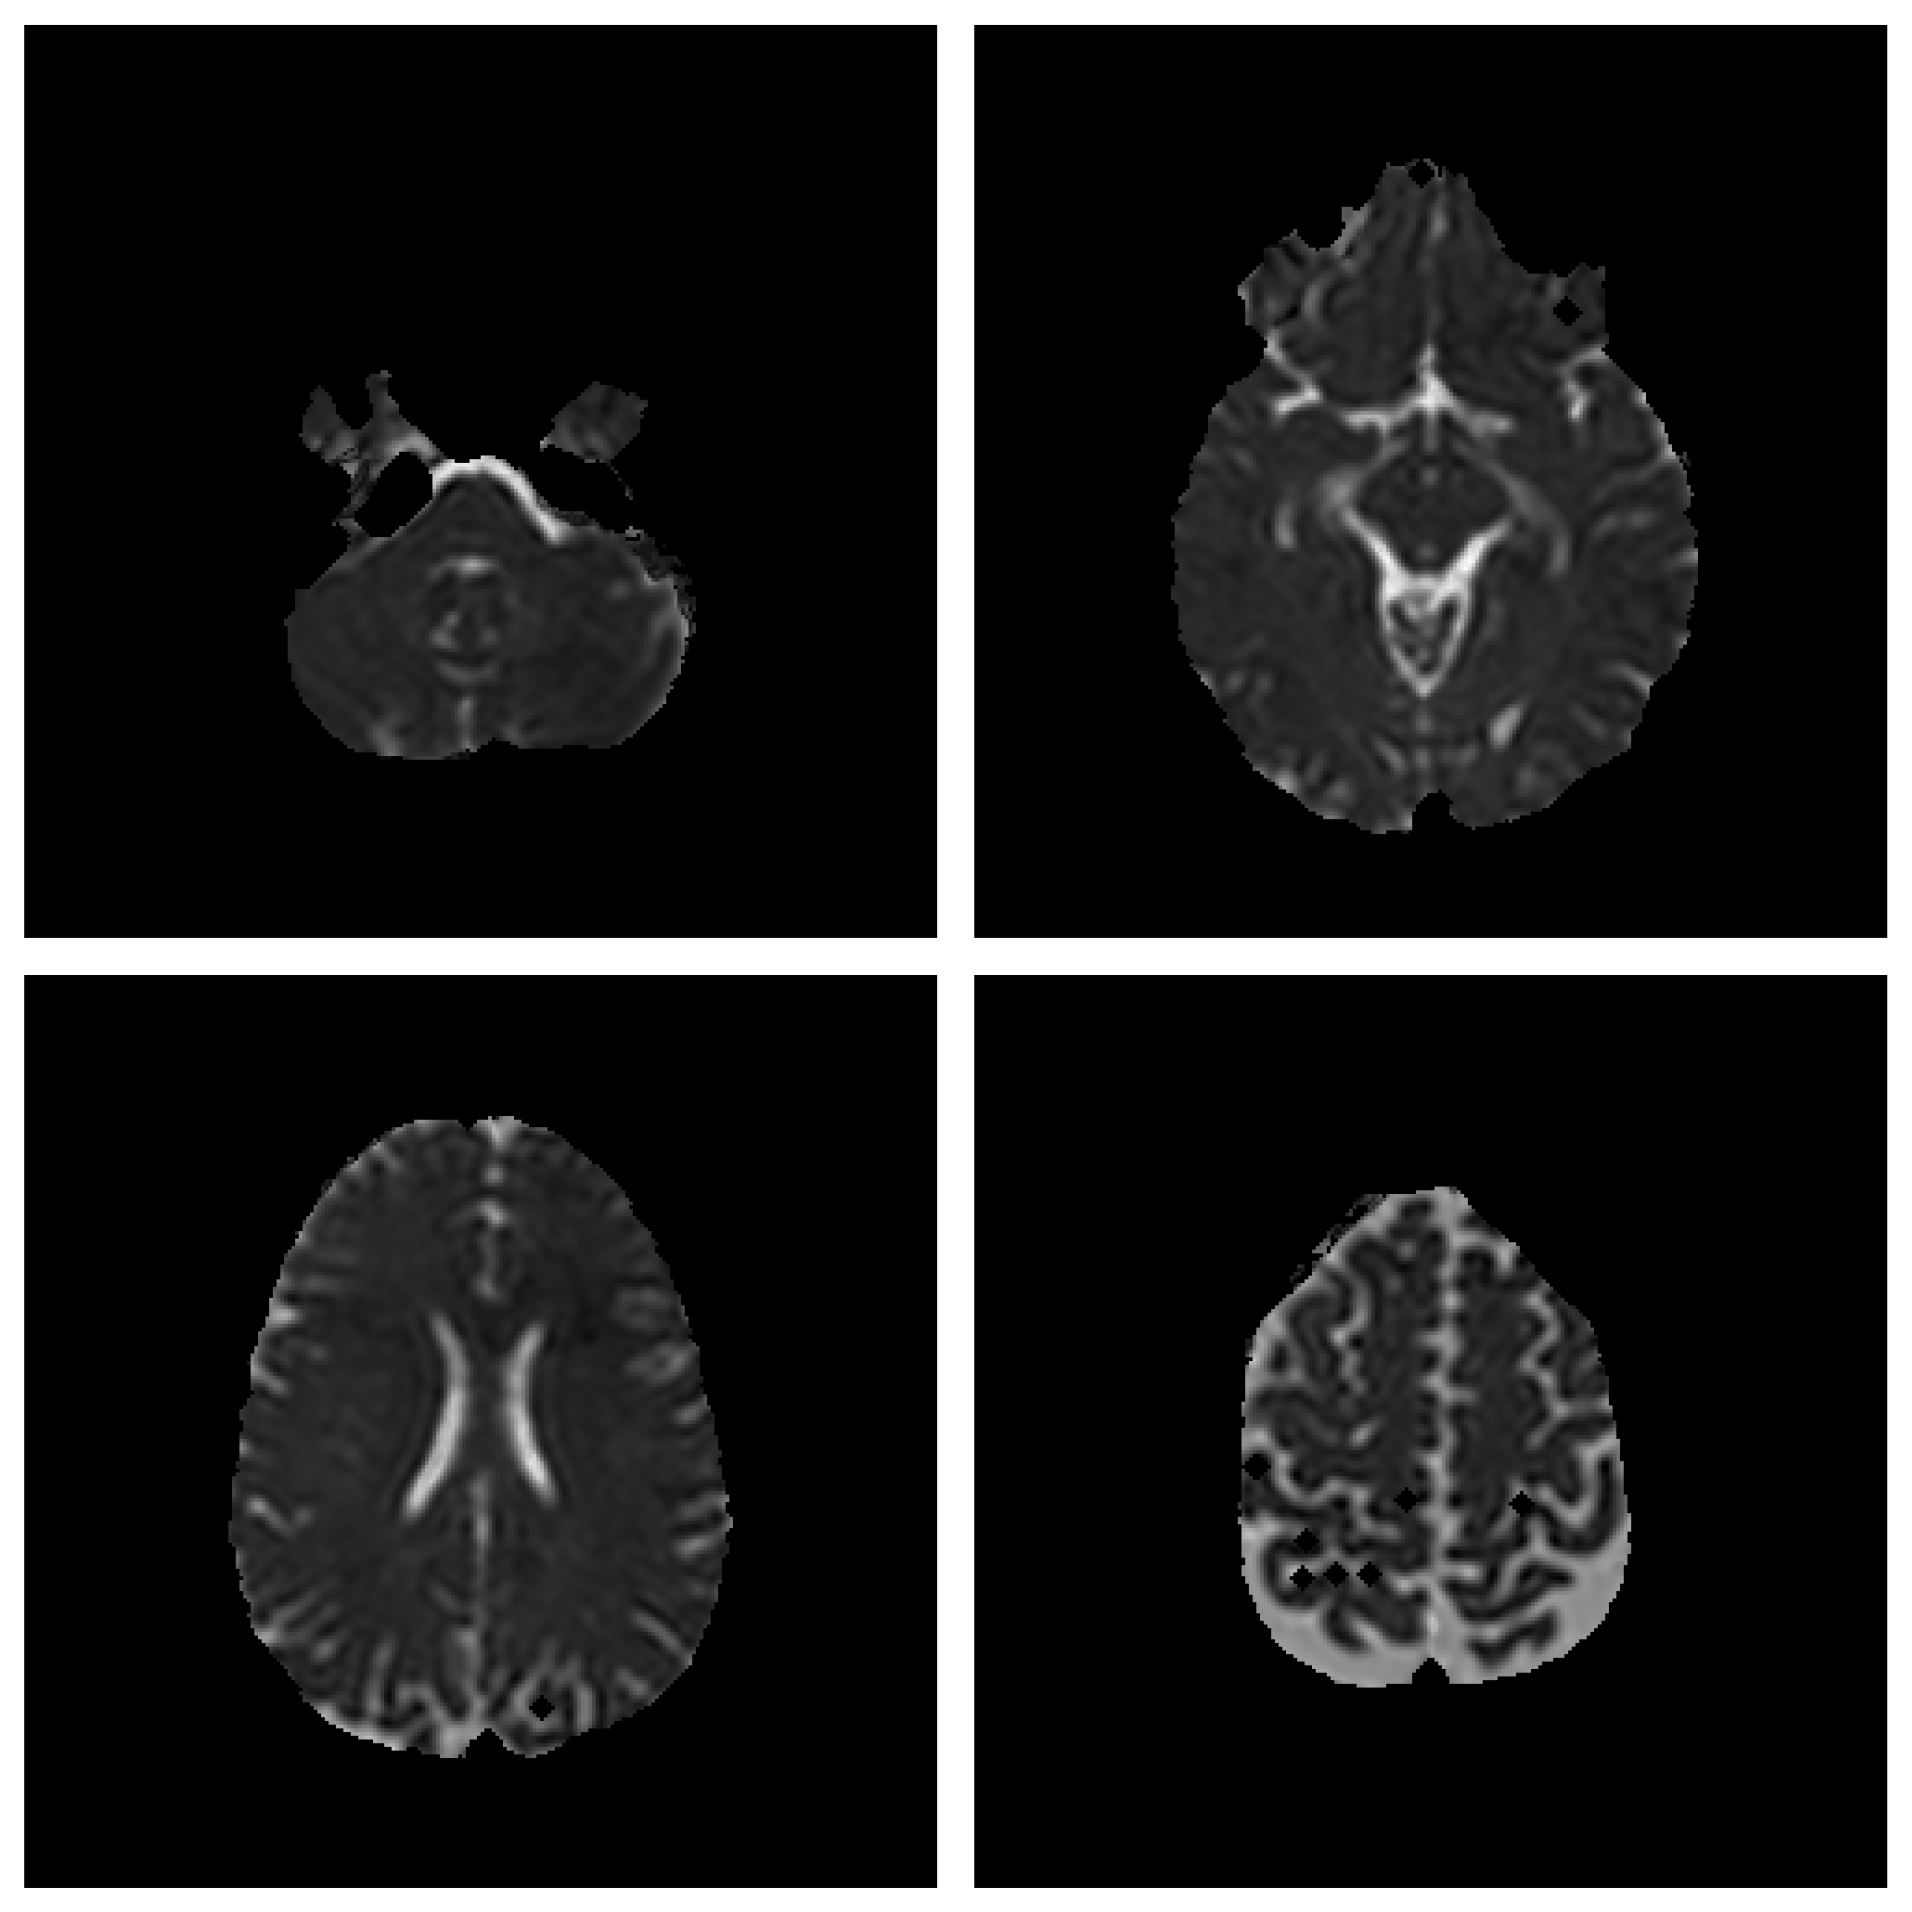

3.1. Image Clustering Utility

- Histogram Quantization

- K-Means

- Fuzzy C-Means (FCM)

- Expectation Maximization (EM)

- Iterated Conditional Mode (ICM)